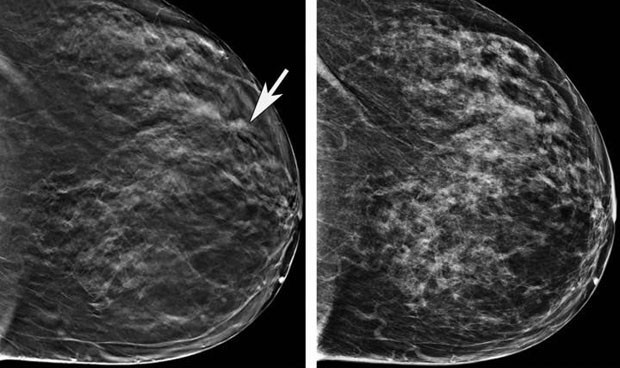

La resonancia magnética se sitúa como técnica de elección entre las mujeres de alto riesgo.

“Desde la Sociedad Española de Diagnóstico por Imagen de la Mama (Sedim) se apoya la bajada de edad del cribado del cáncer de mama y su prolongación hasta los 75 años siguiendo las directrices europeas. En el caso de las mujeres de alto riesgo la resonancia magnética se sitúa como técnica de elección” comenta Romero. Además, “todas estas medidas se toman a raíz de la demostración de que los cribados en este rango de edad disminuyen la mortalidad por cáncer de mama y favorecen tratamientos más inocuos paras las mujeres”, puntualiza la especialista.